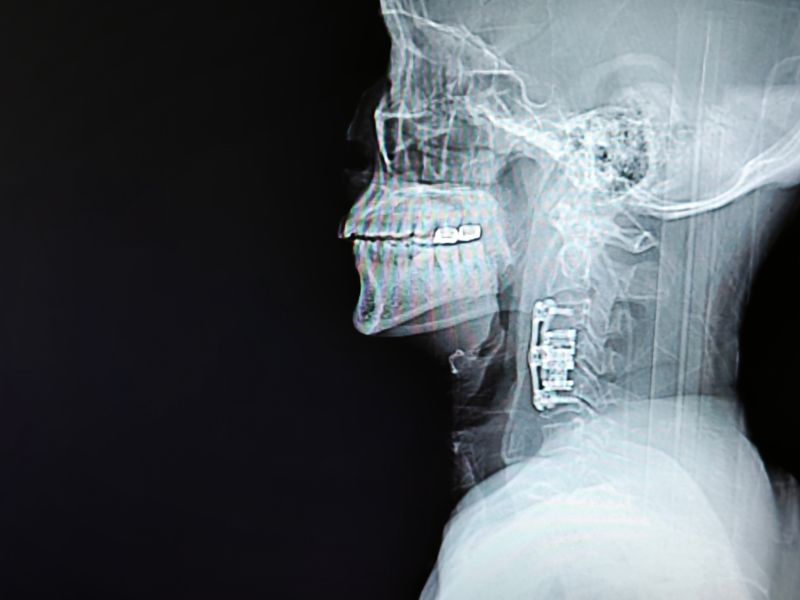

神经外科团队于3月27日为患者实施"右侧前入路C4椎体及椎间盘切除+人工椎体置入术",彻底解除脊髓压迫并重建脊柱力学结构。术后影像学显示人工椎体对位良好,脊髓减压充分。